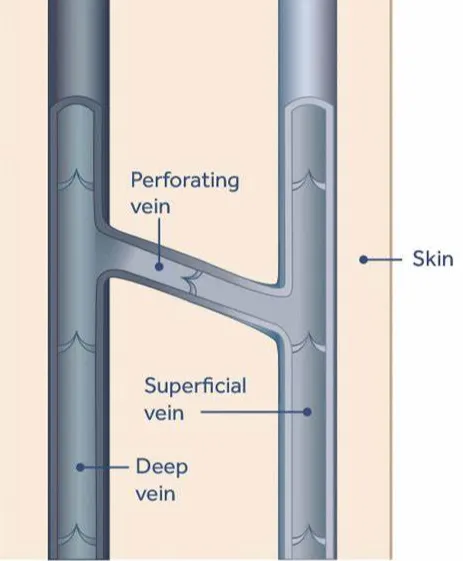

TIPS: 下肢静脉层级网络

覆盖隐静脉表面的筋膜称为“隐筋膜”,其与深筋膜之间的间隙称为“隐筋膜室”。下肢静脉至此刻划分为三个解剖层次,即:深层(深筋膜之下);筋膜间层(深筋膜与隐筋膜之间,即皮下深层)和皮下层(皮肤与隐筋膜之间,即皮下浅层)。

Franceschi和Zamboni将其称为解剖筋膜室 (anatomical compartment, AC),三层分别为AC1、AC2和AC3,其内走行的静脉分别为N1(深静脉系统)、N2(大隐静脉系统)和N3(大隐静脉属支)。